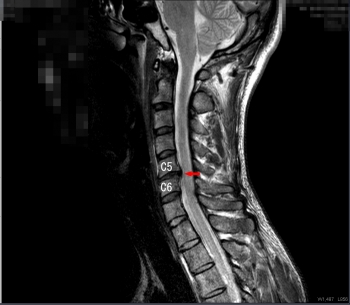

頚椎椎間板ヘルニア

椎骨について

頚からお尻まで繋がっている脊椎(背骨)は長い一本の骨ではなく、椎骨というブロック状の骨がいくつも重なってできています。

椎間板について

椎骨と椎骨の間には椎間板という柔らかい軟骨があり、クッションの役割をしています。

神経の圧迫について

その椎間板の中身の髄核が飛び出て、頚椎の中の神経が圧迫されて、痛みやコリ、痺れなどが現れます。

比較的若い方に多い病気です。